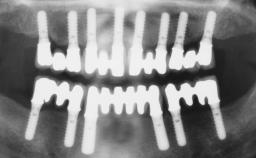

A 63-year-old male patient was referred for a consultation and treatment of partial edentulism in the maxilla. The patient presented with residual anterior teeth and declined a partial removable prosthesis. He reported that the maxillary posterior teeth had been extracted due to mobility and periodontal disease two months before the consultation. The patient’s chief complaint was that his residual maxillary teeth were mobile and that he was unable to chew. The patient’s desire was a stable and comfortable fixed maxillary rehabilitation. The patient was a light smoker (fewer than 10 cigarettes/ day), and his medical history was without significant findings. He was not on any regular medication at the time of consultation. The extraoral examination revealed a normal physiognomy with a correct distribution of the facial thirds. The patient presented a low lip line, and the transition line between teeth and soft tissues was not exposed during a forced smile.

| # of Implants | 6 |

| Type of Implants | One-Piece |

| Attachment | One-Piece |